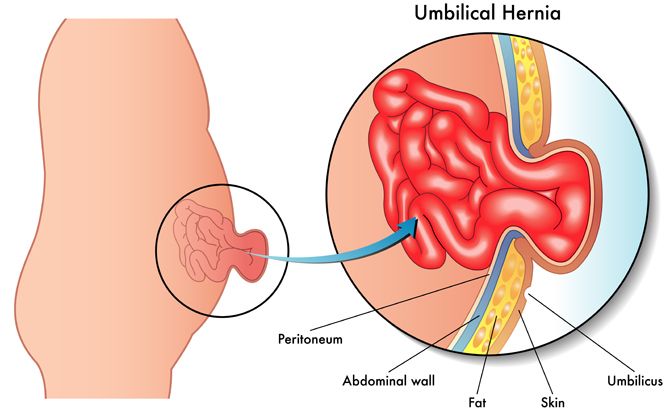

Laparoscopic Hernia Surgery

Stable and long-lasting hernia repair using minimally invasive surgical methods.